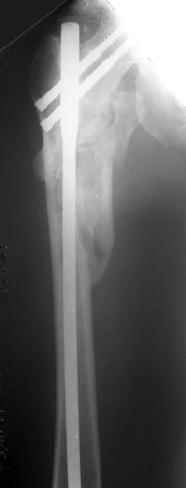

Другое наблюдение:Мужчина, 1957 г.р. Травма в результате ДТП 12.09.04г.

Диагноз: Закрытый оскольчатый подвертельный перелом правой бедренной кости со смещением отломков, оскольчатый перелом большого вертела, отрывной перелом малого вертела.Сопутствующие заболевания: Язвенная болезнь желудка, ремиссия.

Наверно, можно и так сказать, но можно и тоже самое - 4-фрагментный вертельный перелом. Выбор тот же, но с учетом молодого возраста реконструкционный гвоздь тут более применим. Вот уже наш пример.

В данной ситуации я бы провел остеосинтез при использовании длинного Gamma Nail

Вправление не было бы идеальным но операция закрытым доступом была бы меннее тяжелой так же как и ее последствия .